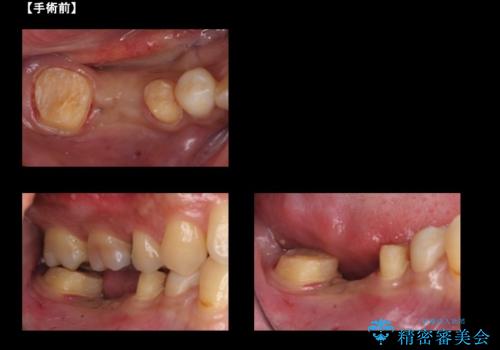

右下の奥歯の虫歯が大きく、やりかえが難しい状態でした。

外して虫歯を取ったところ。歯茎の深いところまで虫歯があり、やむなく抜歯しました。

手術はディスタルウェッジとAPFを併せて行なっています。

右下6については、物理的には歯を使うことは可能ですが、残すと悪くなっていくのを避けられないような修復しかできないため、長期的な展望が立たないため抜歯をお勧めしました。

短期的にまた抜歯になるような修復のやりかえは、お勧めしておりません。